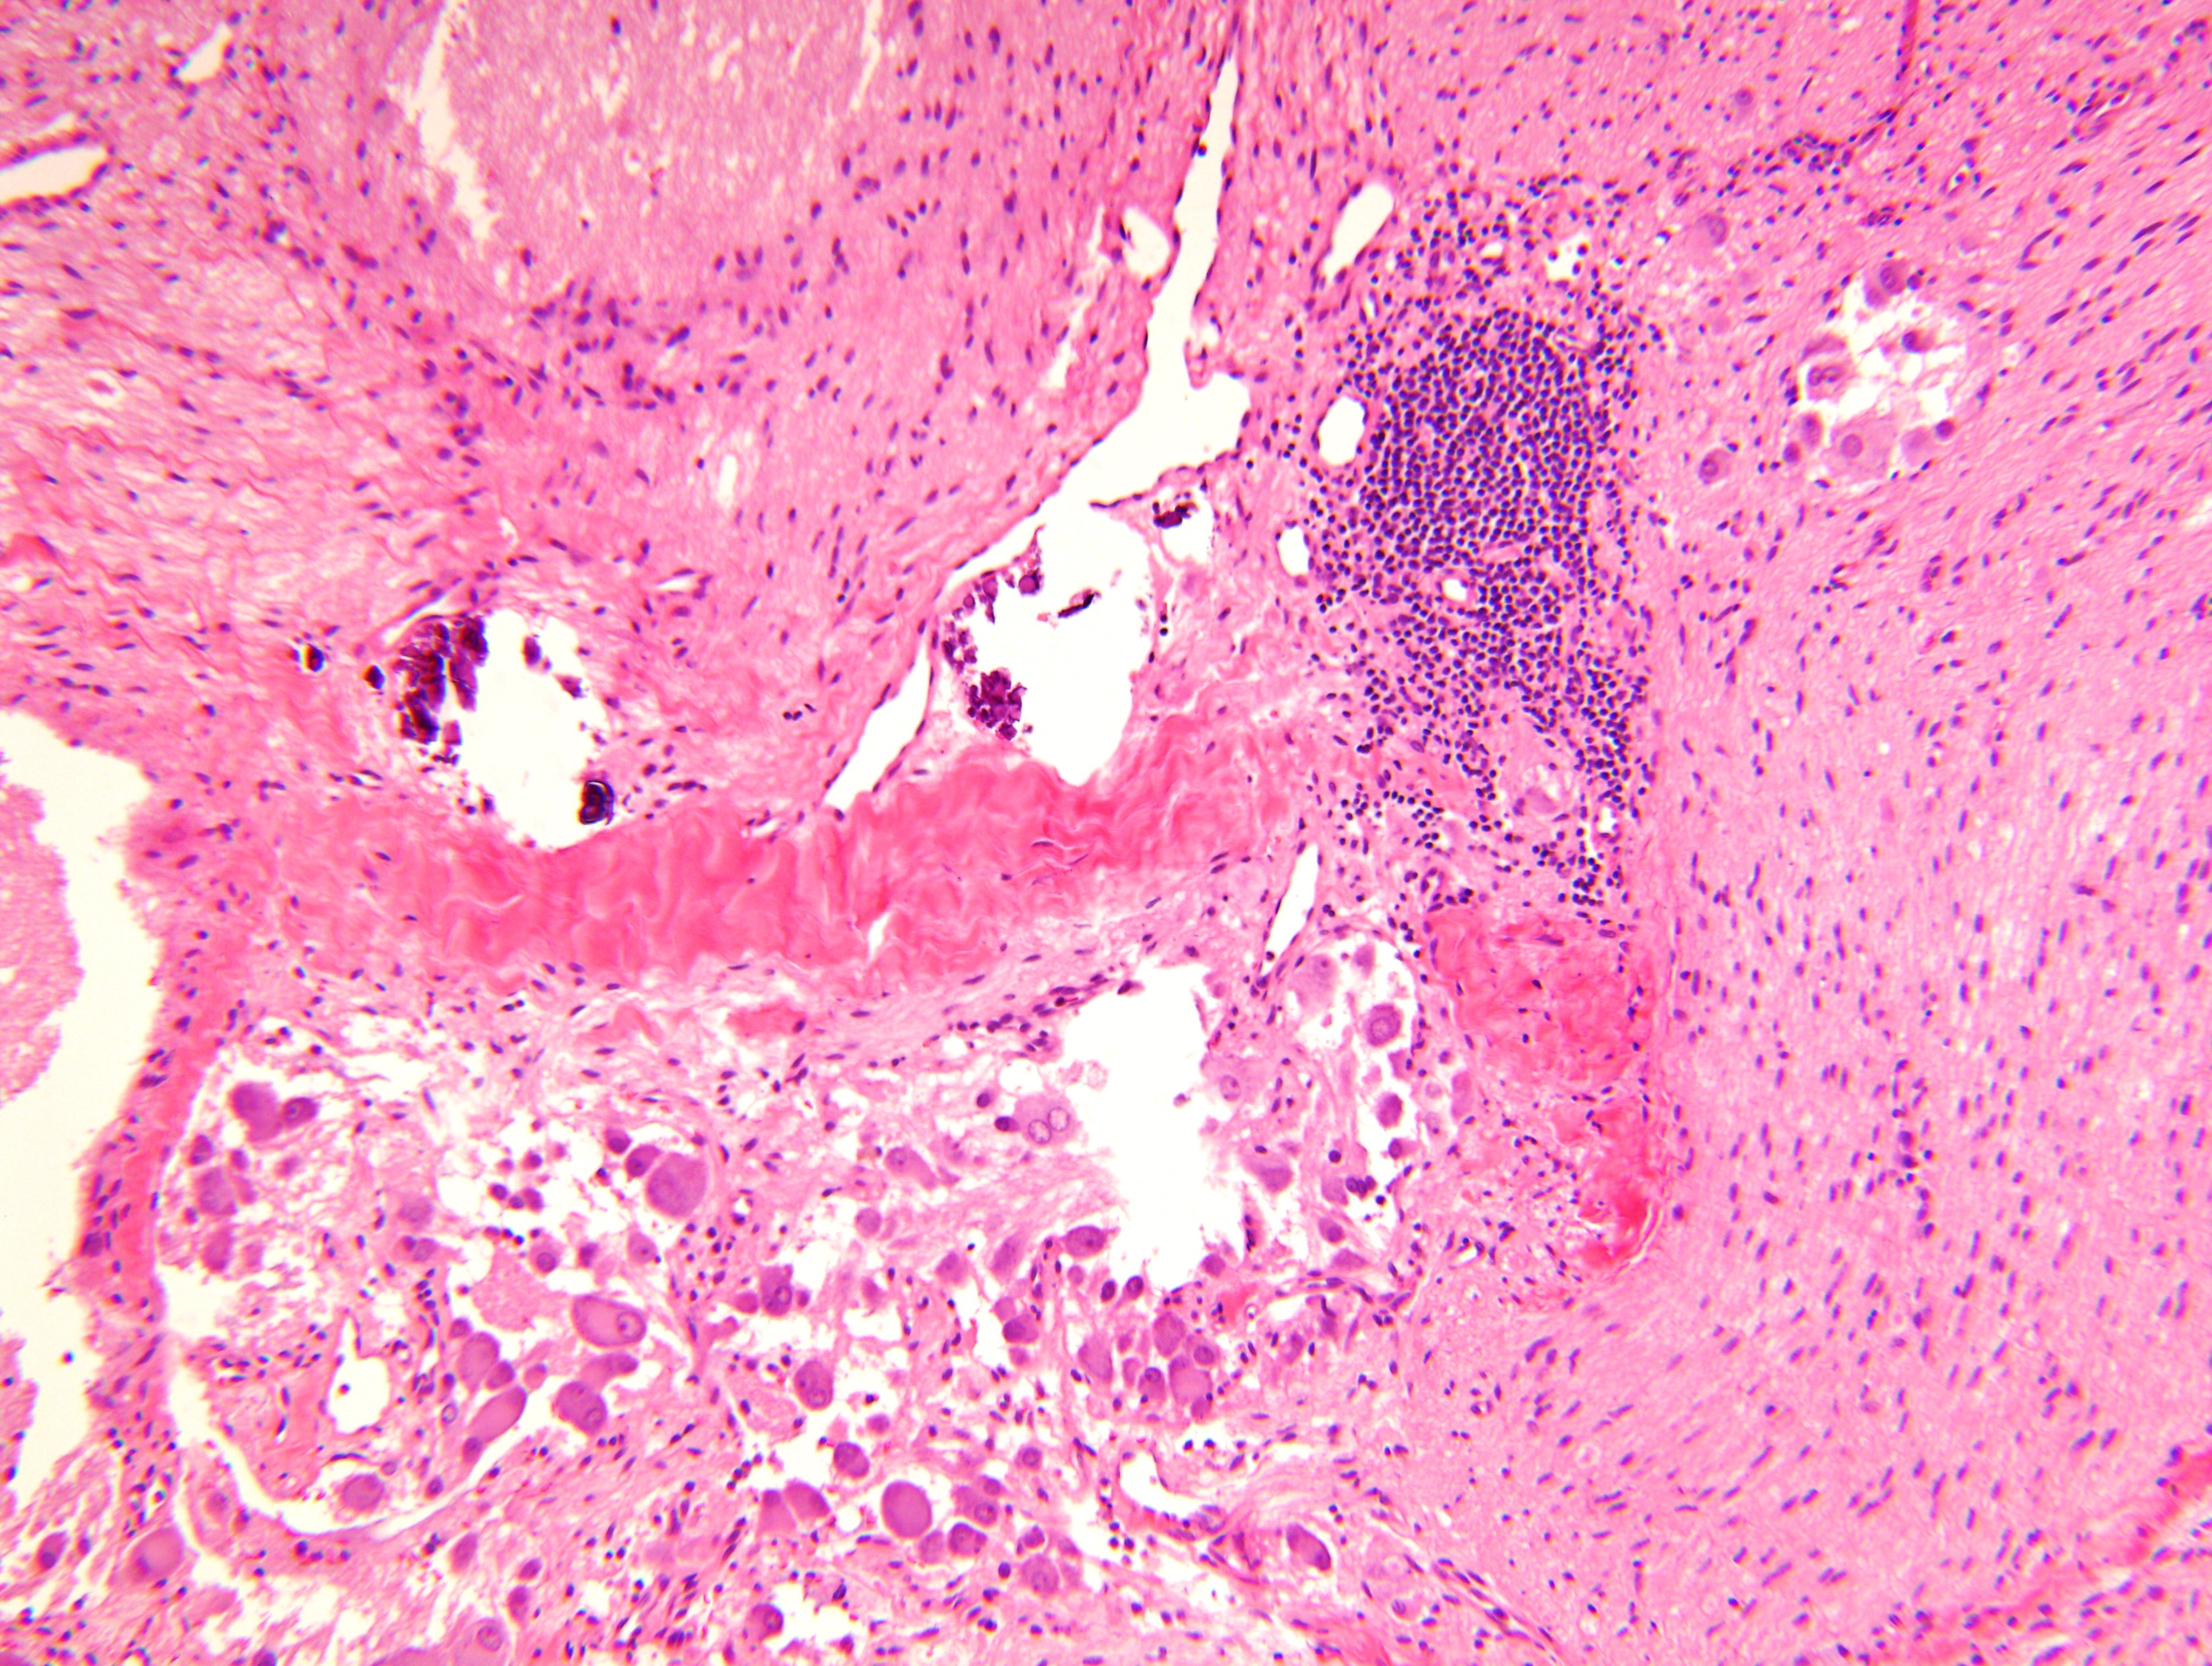

Microscopic (histologic) description

- Architecture: lobular, diffuse / solid, organoid

- Ganglion cells

- Abundant granular eosinophilic cytoplasm (Nissl substance = rough endoplasmic reticulum)

- Distinct cell borders

- Nuclear enlargement, eccentric nuclei, prominent nucleoli

- May see neuromelanin pigment (brown, finely granular; rarely present), cystic degeneration, hemorrhage, dystrophic calcification

Microscopic (histologic) images

Contributed by Carmen Perrino, M.D. and Debra L. Zynger, M.D.

Nodular type